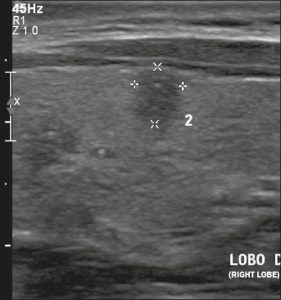

Hình 18. Hình ảnh nhân giáp dạng đặc (2 điểm), đồng âm (1 điểm), rộng hơn cao (0 điểm), có bờ trơn láng (0 điểm) và không có các ổ tăng âm hay bóng lưng (0 điểm). Do đó, tổng điểm là 3 điểm và mức độ nguy cơ được phân loại là TR3.